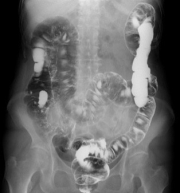

上部消化管検査

下部消化管検査